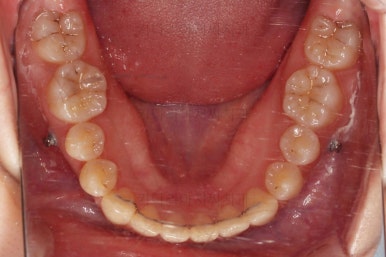

입 안을 보면 밑에 치열이나 다른 부분은 비교적 양호한데 유달리 윗니 송곳니만 위치가 좋지 못하네요.

충치가 곳곳에 보이는데요.

성인들은 충치가 멈춰있는 정지우식일 가능성도 있으며 크기가 현재 크지 않고 향후 변화되지 않는다면 그대로 두기도 합니다.

이번 환자분도 교정치료에 방해되는 부분이나 급해보이는 추료만 우선 진행하고 교정 중에 충치가 커지는지 증상이 생기는지 관찰해 보기로 했습니다.

덧니가 완전히 개선디ㅗ었고 필요한 충치치료도 부분적으로 진행했고요.

중앙선이나 교합도 양호하게 마무리 했습니다.

충치도 틀린그림 찾기 수준으로 진짜 필요한 몇 개만 치료를 하고 연산동교정치과 마무리를 했습니다. 어차피 유지관리 체크를 꾸준히 내원하실 거기 때문에 지켜보기로 했습니다.